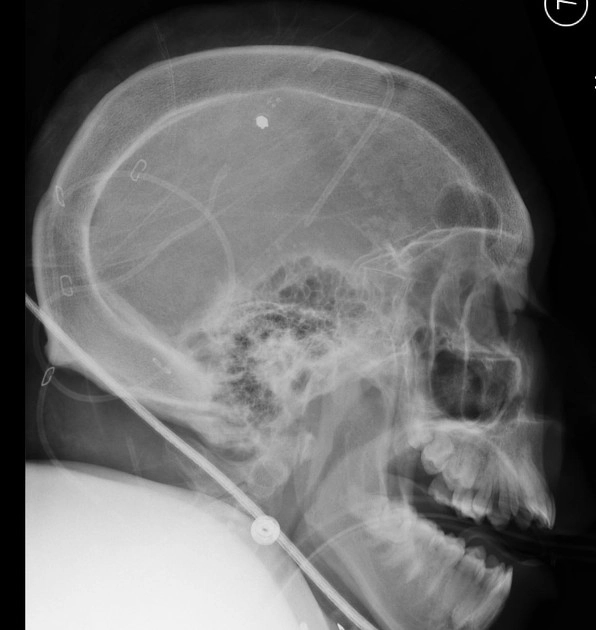

• Bệnh Paget xương sọ - Paget disease (skull)